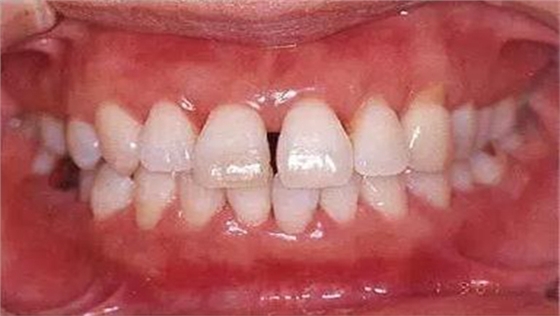

●參考病例① 35歲女性

35歲女性。妊娠4個(gè)月。過(guò)去雖然接受過(guò)刷牙指導(dǎo),但菌斑控制狀態(tài)依然不理想?;颊哂邪l(fā)現(xiàn)自己刷牙時(shí)牙齦出血。